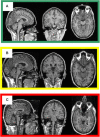

High-resolution three-dimensional magnetic resonance imaging (3D-MRI) is being increasingly used to delineate morphological changes underlying neuropsychiatric disorders. Unfortunately, artifacts frequently compromise the utility of 3D-MRI yielding irreproducible results, from both type I and type II errors. It is therefore critical to screen 3D-MRIs for artifacts before use. Currently, quality assessment involves slice-wise visual inspection of 3D-MRI volumes, a procedure that is both subjective and time consuming. Automating the quality rating of 3D-MRI could improve the efficiency and reproducibility of the procedure. The present study is one of the first efforts to apply a support vector machine (SVM) algorithm in the quality assessment of structural brain images, using global and region of interest (ROI) automated image quality features developed in-house. SVM is a supervised machine-learning algorithm that can predict the category of test datasets based on the knowledge acquired from a learning dataset. The performance (accuracy) of the automated SVM approach was assessed, by comparing the SVM-predicted quality labels to investigator-determined quality labels. The accuracy for classifying 1457 3D-MRI volumes from our database using the SVM approach is around 80%. These results are promising and illustrate the possibility of using SVM as an automated quality assessment tool for 3D-MRI.